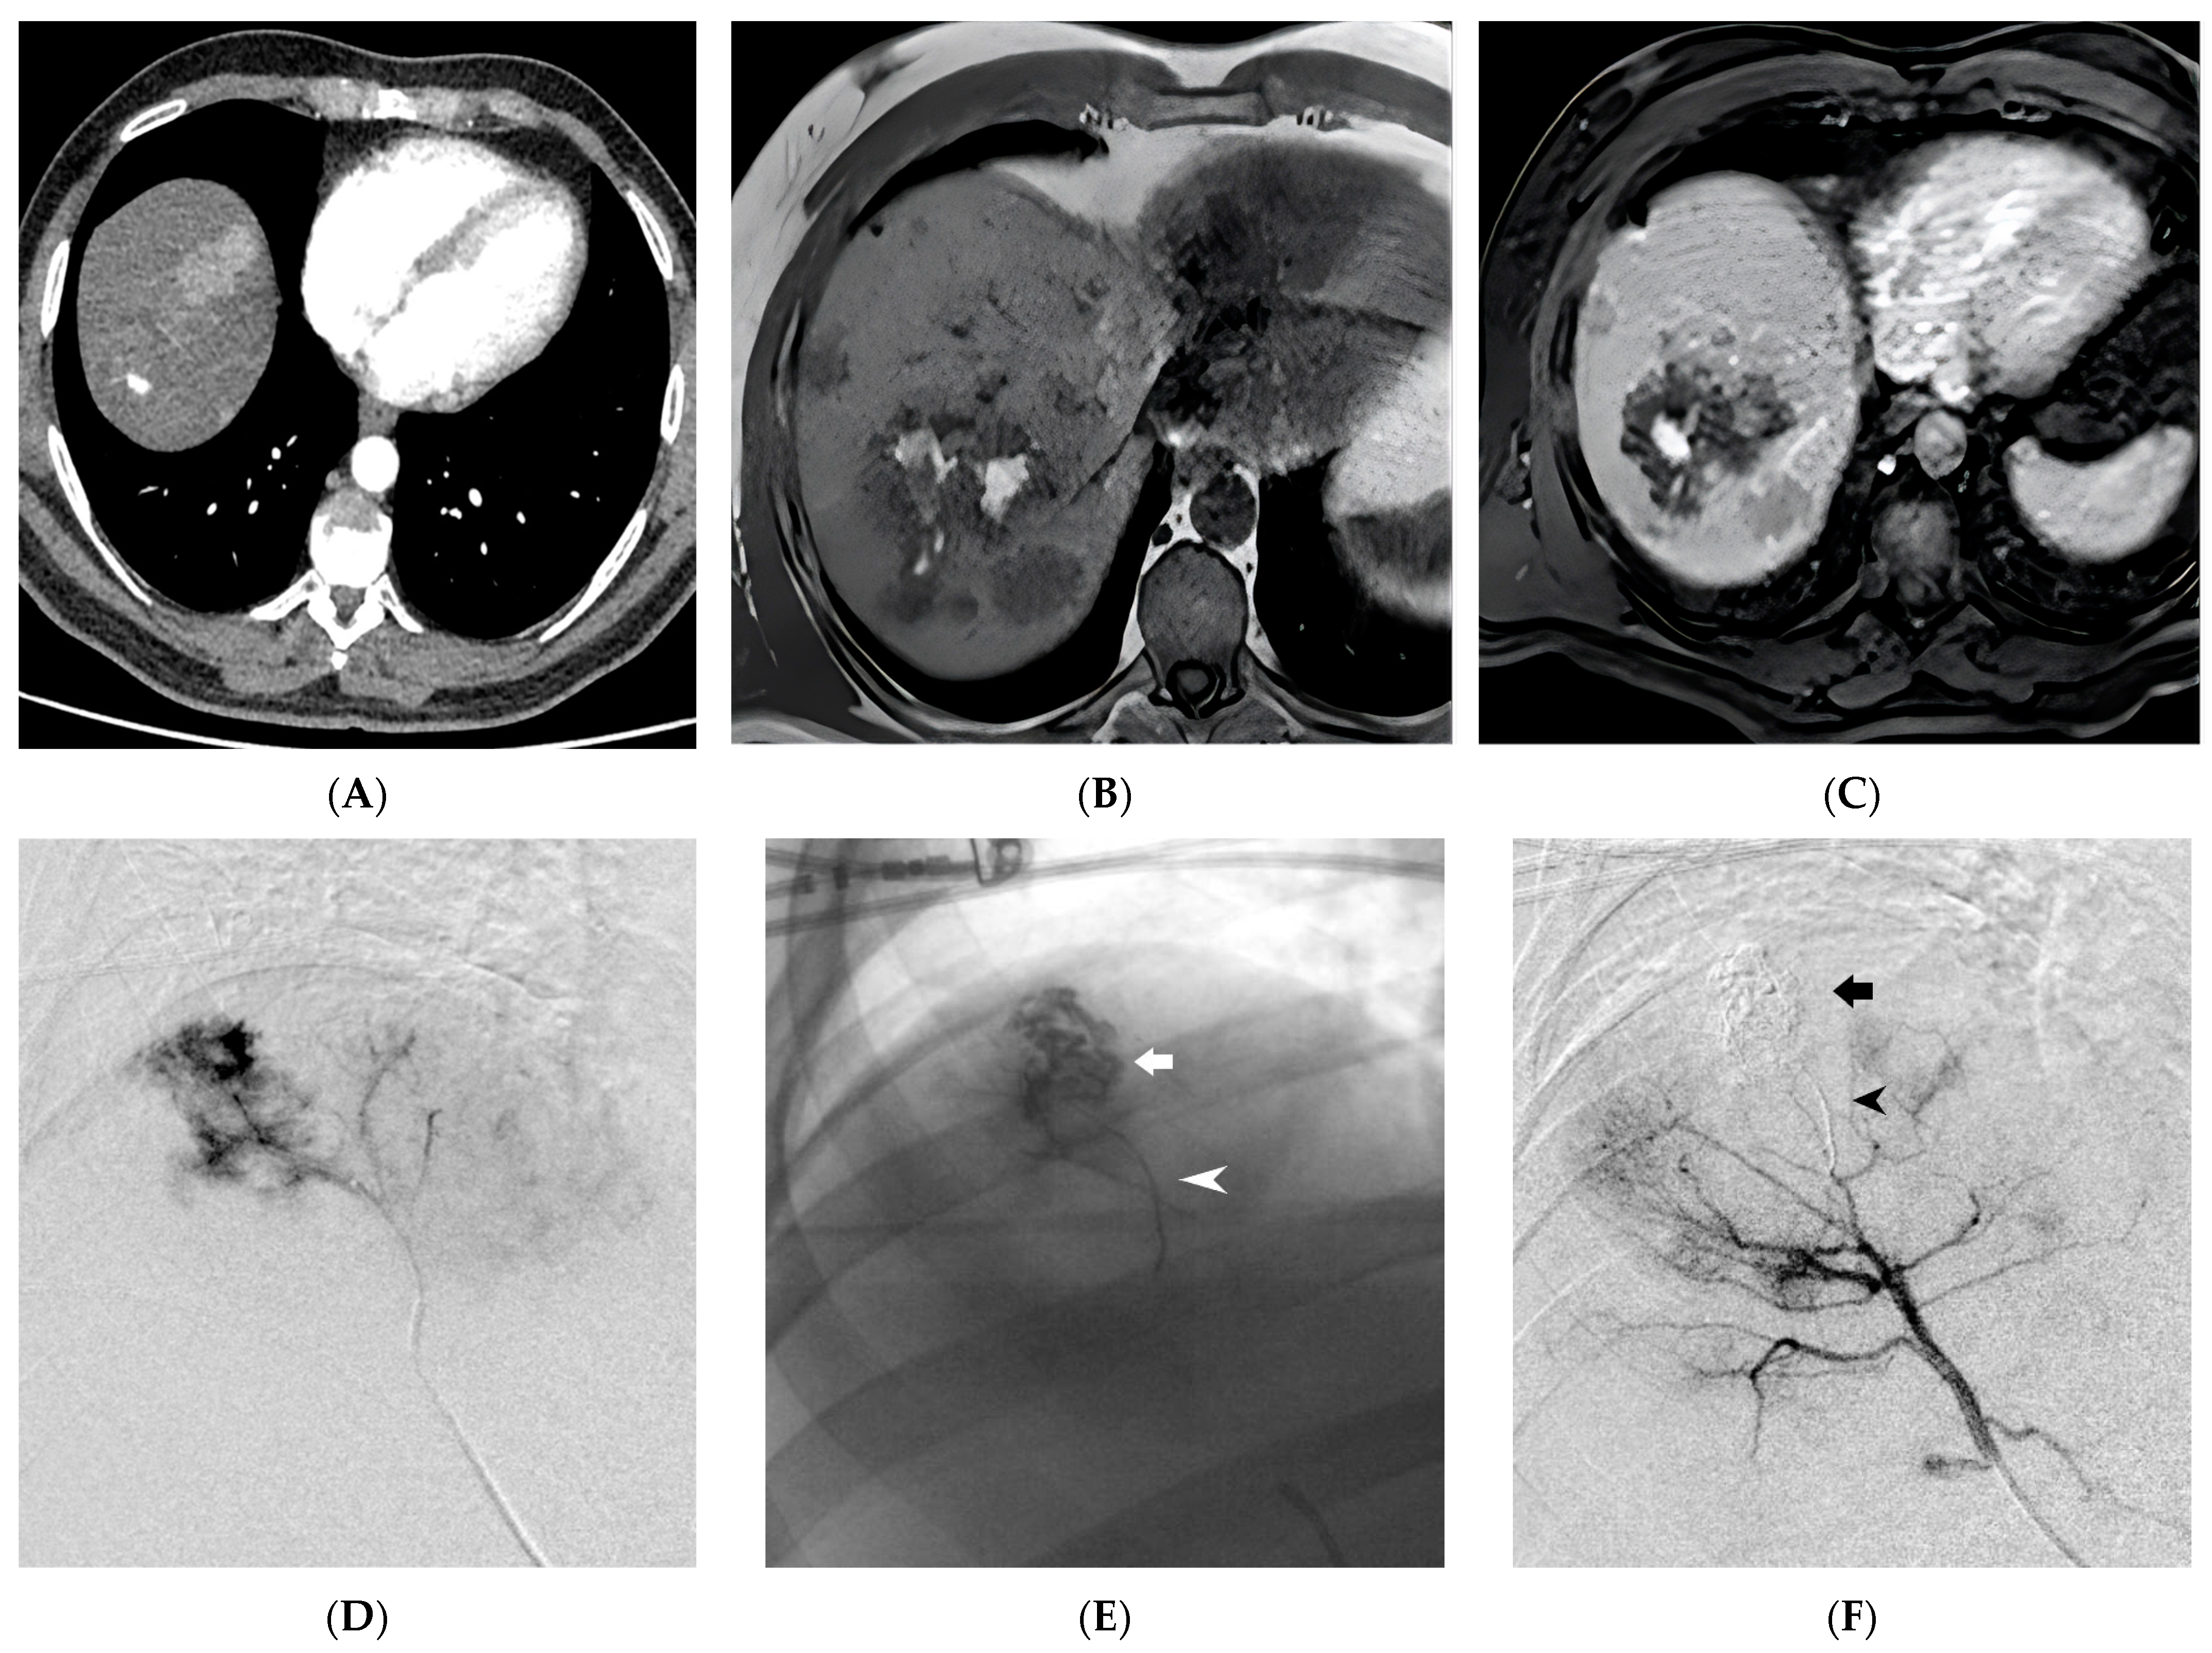

Figure 3. Ruptured Hepatocellular Carcinoma (HCC) within the hepatic parenchyma is depicted in the images. In the contrast-enhanced Computed Tomography, arterial phase, there is evidence of a 1 cm pseudoaneurysm within an HCC nodule (A). On the Magnetic Resonance Imaging (MRI) T1 Fast Field Echo In-Phase sequence, hyperintense material (blood) is observed within a large HCC nodule of the right lobe (B). Gadobenate dimeglumine (Gd-BOPTA)-enhanced MRI in the arterial phase confirms the presence of an intranodular contrast blush (C). Superselective digital subtraction angiography of the S7 hepatic artery branch shows contrast leakage into the ruptured HCC (D). Successful embolization of the HCC nodule (indicated by the arrow) and the parent artery (indicated by the arrowhead) was achieved using Ethylene-Vinyl Alcohol (EVOH) copolymer (E,F). (From Minici et al. doi: 10.3390/medicina59040710, by MDPI, Basel, Switzerland, licensed under CC BY 4.0).